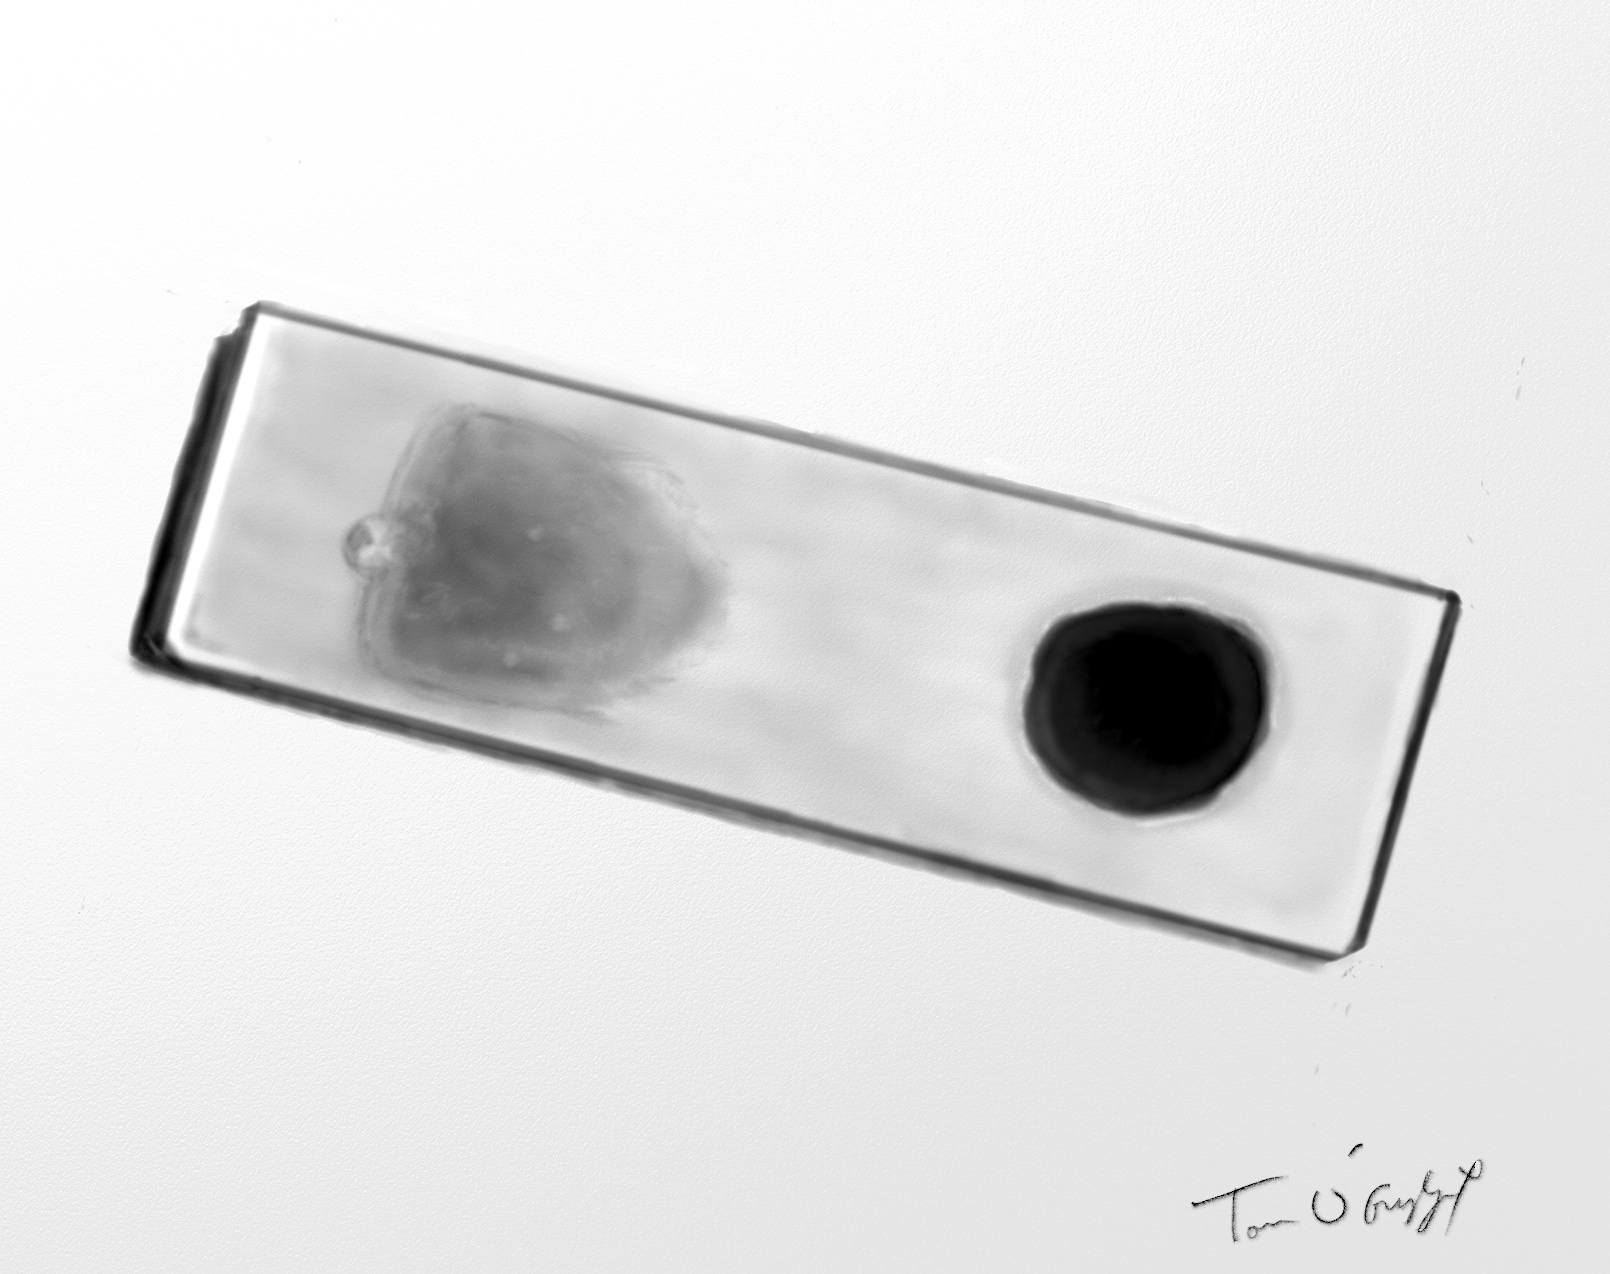

paludisme frottis goutte epaisse

frottis sanguin à gauche et goutte épaisse à droite sur la même lame pour le diagnostic de paludisme au microscope

Il doit se faire en urgence, nécessitant la lecture d’une lame d’un frottis sanguin. En cas de négativité on utilise  la technique de la goutte épaisse, par concentration du sang pour avoir plus de chances d’observer des parasites au microscope, d’identifier l’espèce et de quantifier la parasitémie. Sa sensibilité est nettement supérieure au frottis mais elle demande du temps, les deux méthodes sont souvent réalisées parfois sur la même lame. Le diagnostic au microscope optique est parfois difficile pour les trophozoïtes (formes en anneaux très similaires pour toutes les espèces).